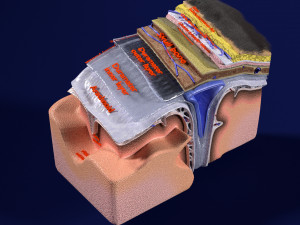

A blend model of brain along with its covering layers (meninges), skull bone and scalp labelled in detail and anatomically precise. The parts depicted are white, gray, pia, arachnoid, dura, bone, skin, fat, aponeurosis, periosteum, falx cerebri and more.

The material is high resolution image textures and normal maps based on non overlapping UVs. The texture and normal maps are packed with the blend file itself.